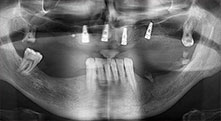

Un paciente de 40 años con una dentadura restante desastrosa desea someterse a un tratamiento mediante implantes. Como es fumador, en el maxilar superior no se planea una elevación del seno con prótesis dental fija, sino una prótesis mediante puente sobre cuatro implantes anteriores.

Implantes

Los cuatro implantes se encuentran in situ tal como estaba planeado. Los molares distales del maxilar superior sirven además para fijar la prótesis con base reconstruida, que se monta un mes después de la implantación.